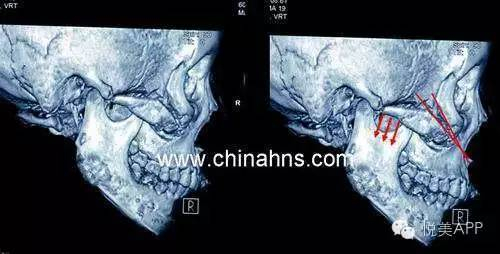

首先我们来了解一下颧骨内推的术式

总的来说颧骨手术就是:前方从口腔内切口进入,后方从耳前切口进入,剥离开截骨部分组织之后,在骨膜下方操作,截骨后固定。

口腔内切口,剥离组织

切割颧骨

耳前切口

颧骨部位L型切口,去掉部分骨头,如图示

向内推移,并前后用钛钉固定

最后呈现颧骨降低,正面脸变窄的效果